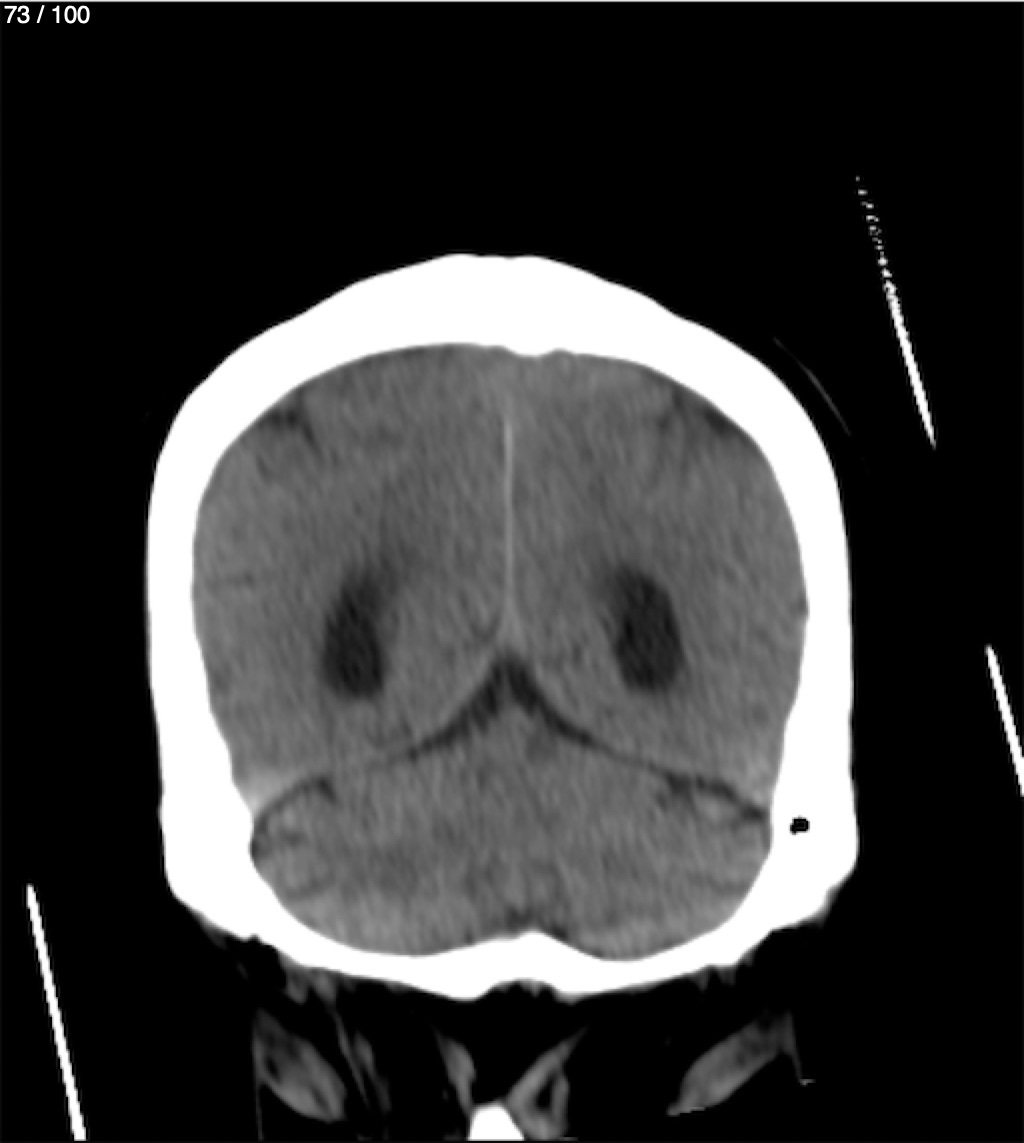

Jose Sosa Martinez 66A - Angiotac Craneo